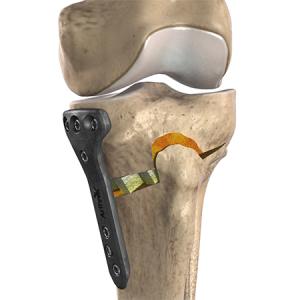

Operative Therapie: Umstellungsosteotomie

Bei Vorliegen einer unphysiologischen Beinachse kann die Belastungsachse des Beines auf die innere (O-Bein) oder äussere (X-Bein) Seite des Kniegelenkes verlagert sein und somit zu isolierten Verschleißerscheinungen führen. In den Fällen mit einer einseitigen Schmerzsymptomatik kann mit einer Achskorrektur eine Schmerzbefreiung erzielt und ein Fortschreiten des Knorpelschadens aufgehalten werden. Vorteil dieser Operation ist, dass das Kniegelenk mit seinen Bändern vollständig erhalten bleibt und mit anderen erhaltenden Operationen wie einer Knorpelbehandlung kombiniert werden kann. Vor einem solchen Eingriff wird anhand einer Spezialaufnahme genau berechnet, an welcher Stelle der Fehler genau liegt und in welchem Maße die Korrektur durchgeführt werden muss.